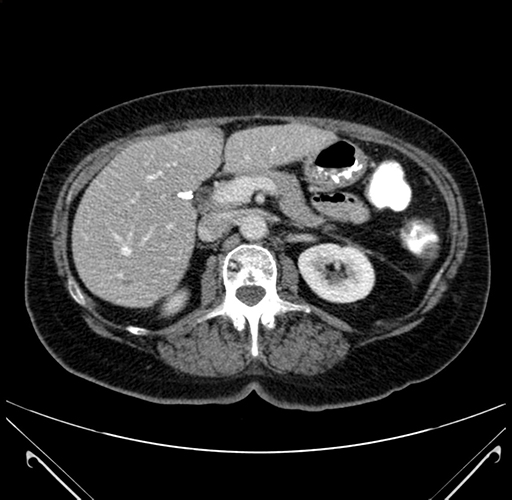

Axial Venous